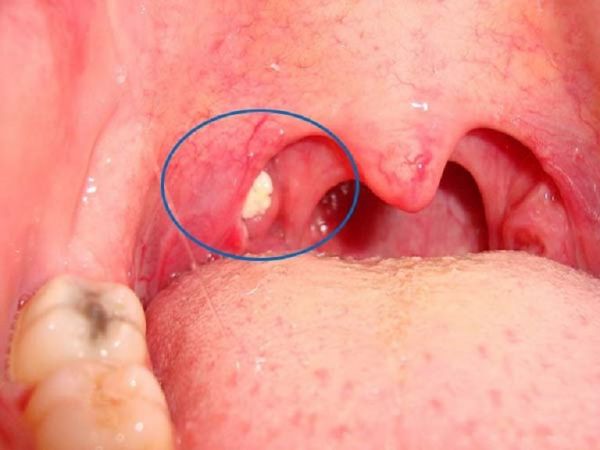

Sỏi amidan là những khối màu trắng hoặc vàng nằm trên hoặc trong amidan. Thông thường, người bệnh sẽ không nhận ra tình trạng này vì rất khó để nhìn thấy khi nhìn bằng mắt thường. Những viên sỏi có kích thước thừ hạt gạo đến quả nho lớn.

Hôi miệng: Một dấu hiệu chính của tình trạng amidan có sỏi là hôi miệng nghiêm trọng đi kèm với nhiễm trùng amidan. Theo một nghiên cứu, khoảng 75% những người bị hôi miệng nặng bất thường đều có sỏi trong amidan. Đau họng: Cả hai tình trạng viêm amidan và sỏi trong amidan đều gây ra đau họng. Tuy nhiên, cơn đau do sỏi gây ra sẽ nặng và khó chịu hơn. Khó nuốt Đau tai: Sỏi có thể xuất hiện bất cứ đâu trên amidan, do đó nó có thể ảnh hưởng đến các dây thần kinh chung dẫn đến tai và khiến bạn bị đau tai. Ho liên tục Sưng amidan Các đốm trắng hoặc vàng trên amidan